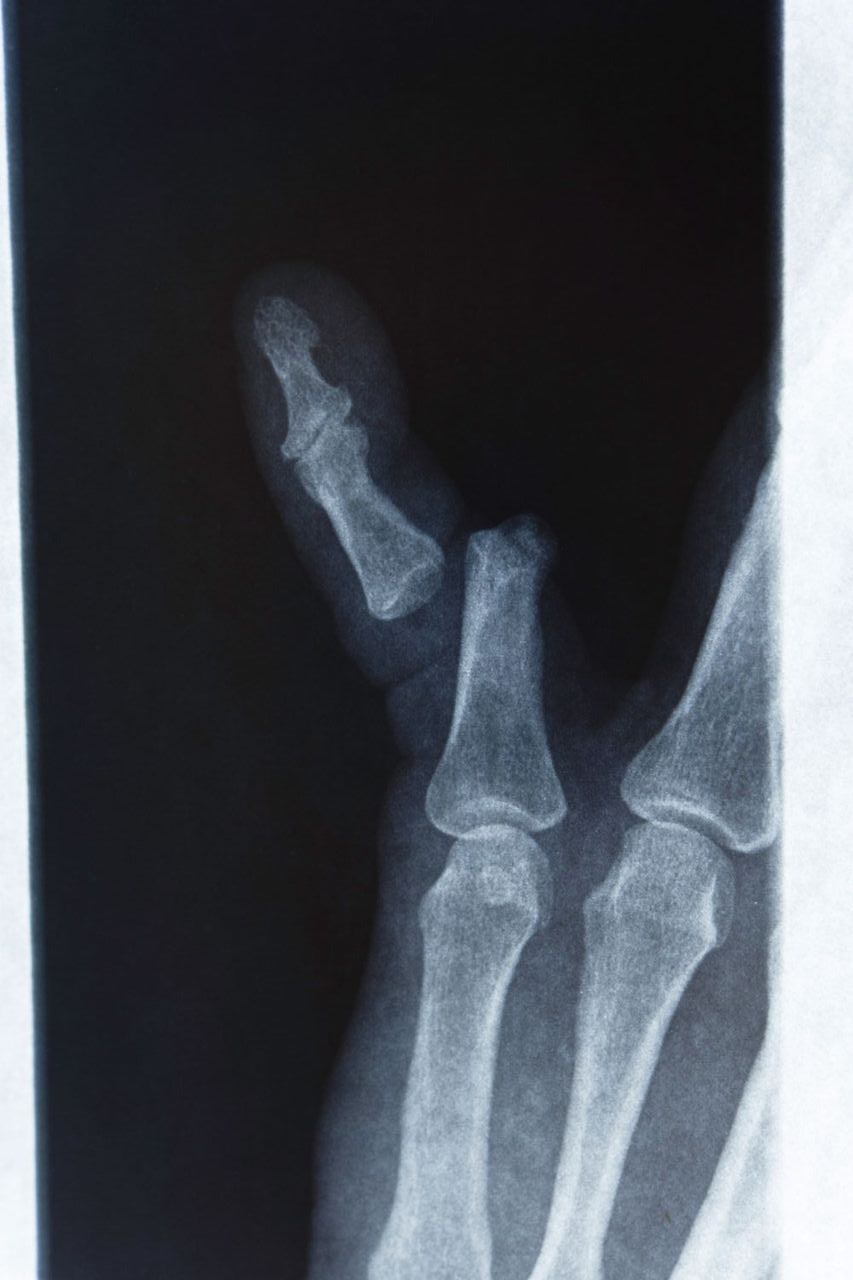

진료비와 검사비

- X-ray 촬영: 기본적으로 뼈 상태를 확인하기 위해 X-ray 촬영이 이루어지며, 병원에 따라 2~5만 원 내외의 비용이 들 수 있습니다.